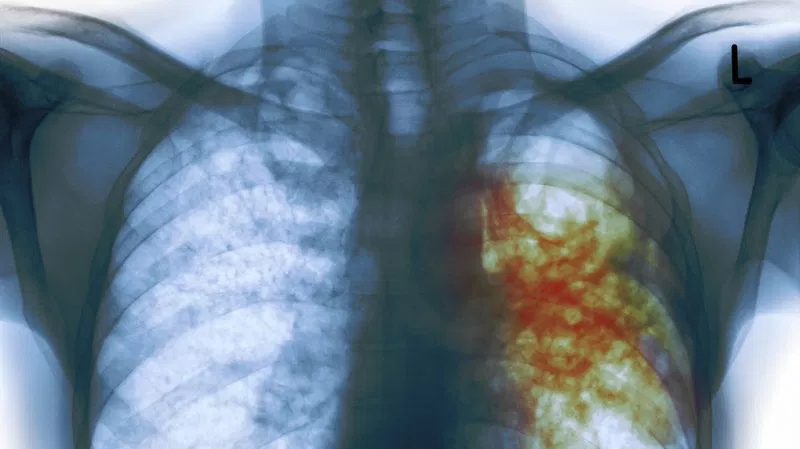

Las bacterias son MO procariotas unicelulares. Sin embargo, muchos forman colonias en forma de biofilms, películas sobre diferentes superficies. Estas colonias les permiten intercambiar genes y nutrientes y protegerse. Las bacterias son los organismos más abundantes y diversos de nuestro planeta y la mayoría son inofensivas o beneficiosas para los humanos (flora bacteriana). Sin embargo, cierto número de bacterias son capaces de producir enfermedades más o menos graves mediante dos mecanismos: Invadiendo directamente los tejidos del hospedador, utilizando sus nutrientes y matando sus células. Por toxigenicidad, es decir, mediante la producción de toxinas, sustancias que actúan como venenos incluso en pequeñísimas cantidades. El número de enfermedades causadas por bacterias es ingente. Entre ellas destacan las siguientes: CÓLERA Bacteria: Vibrio cholerae. Es un bacilo con un flagelo. Provoca grandes epidemias y la muerte de unas 100.000 personas al año. Síntomas: la bacteria fabrica una enterotoxina que provoca vómitos y diarreas que pueden conducir a la deshidratación y la muerte. Transmisión: aguas y alimentos con contaminación fecal. SALMONELOSIS Bacteria: varias especies de Salmonella. Causan fiebres tifoideas, paratifoideas y varios tipos de diarreas. Síntomas: fiebres, vómitos, diarreas (hemorrágicas o no). Transmisión: por agua y alimentos contaminados por heces. TIFUS Bacteria: bacterias del género Rickettsia. Síntomas: fiebre alta, dolores de cabeza y musculares, erupciones cutáneas- Transmisión: por piojos y pulgas de las ratas. BRUCELOSIS O FIEBRE DE MALTA Bacteria: Brucella. Síntomas: fiebre, dolor de cabeza, espalda, y muscular, debilidad Transmisión: contacto con ganado enfermo o consumo de la leche cruda de éste. TÉTANOS Bacteria: Clostridium tetani. Produce una potente neurotoxina, la toxina tetánica. Síntomas: la toxina produce violentos espasmos musculares que pueden conducir a la muerte por parálisis muscular. Se puede prevenir con la vacuna antitetánica o tratar con el suero antitetánico si ya se ha contraído. Transmisión: Sus esporas se hallan en el suelo, estiércol y metales oxidados, por lo que se contrae a través de heridas y mordeduras de animales infectados. MENINGITIS MENINGOCÓCICA Bacteria: bacteria Neisseria meningitidis o meningococo. Síntomas: inflamación de las meninges (membranas que envuelven al sistema nervioso). Provoca rigidez de la nuca, fotosensibilidad, dolor de cabeza. Si llega a la sangre (septicemia) puede ser mortal. Transmisión: por contacto directo con las gotitas de saliva o estornudos de personas contaminadas. Existe vacuna. NEUMONÍA Bacteria: varios tipos de bacterias: Streptococcus pneumoniae (neumococo), Legionella, Mycoplasma, Chlamydia. Síntomas: suele aparecer tras una gripe o catarro. Provoca inflamación pulmonar con acumulación de líquido, dando fiebre, dolor de cabeza, escalofríos, tos, dificultad respiratoria, dolores musculares, debilidad y falta de apetito. Transmisión: a través de microgotas de estornudos y tos de personas enfermas. Es muy habitual en hospitales (enfermedad nosocomial). La mejor prevención es la higiene y el lavado de manos y utensilios. TUBERCULOSIS O TISIS Bacteria: Mycobacterium tuberculosis o bacilo de Koch. Invade los pulmones y son encerradas por el sistema inmune en nódulos o granulomas. Síntomas: si se reactivan los granulomas provocan fiebre, sudores, tos y fatiga con pérdida de peso. Produce graves lesiones pulmonares y óseas. Transmisión: por tos y estornudos de enfermos. Afecta sobre todo a pacientes inmunodeprimidos (leucemia, SIDA). Existe una vacuna y se previene con higiene. GONORREA Bacteria: Neisseria gonorrhoeae o gonococo. Síntomas: en hombres: secreción purulenta en la uretra y dolor al orinar; en mujeres:asintomática o secreción vaginal y molestias al orinar. Si se extiende hacia el útero puede dar esterilidad permanente. Transmisión: contacto sexual con personas infectadas. La mejor prevención es el uso de preservativo.